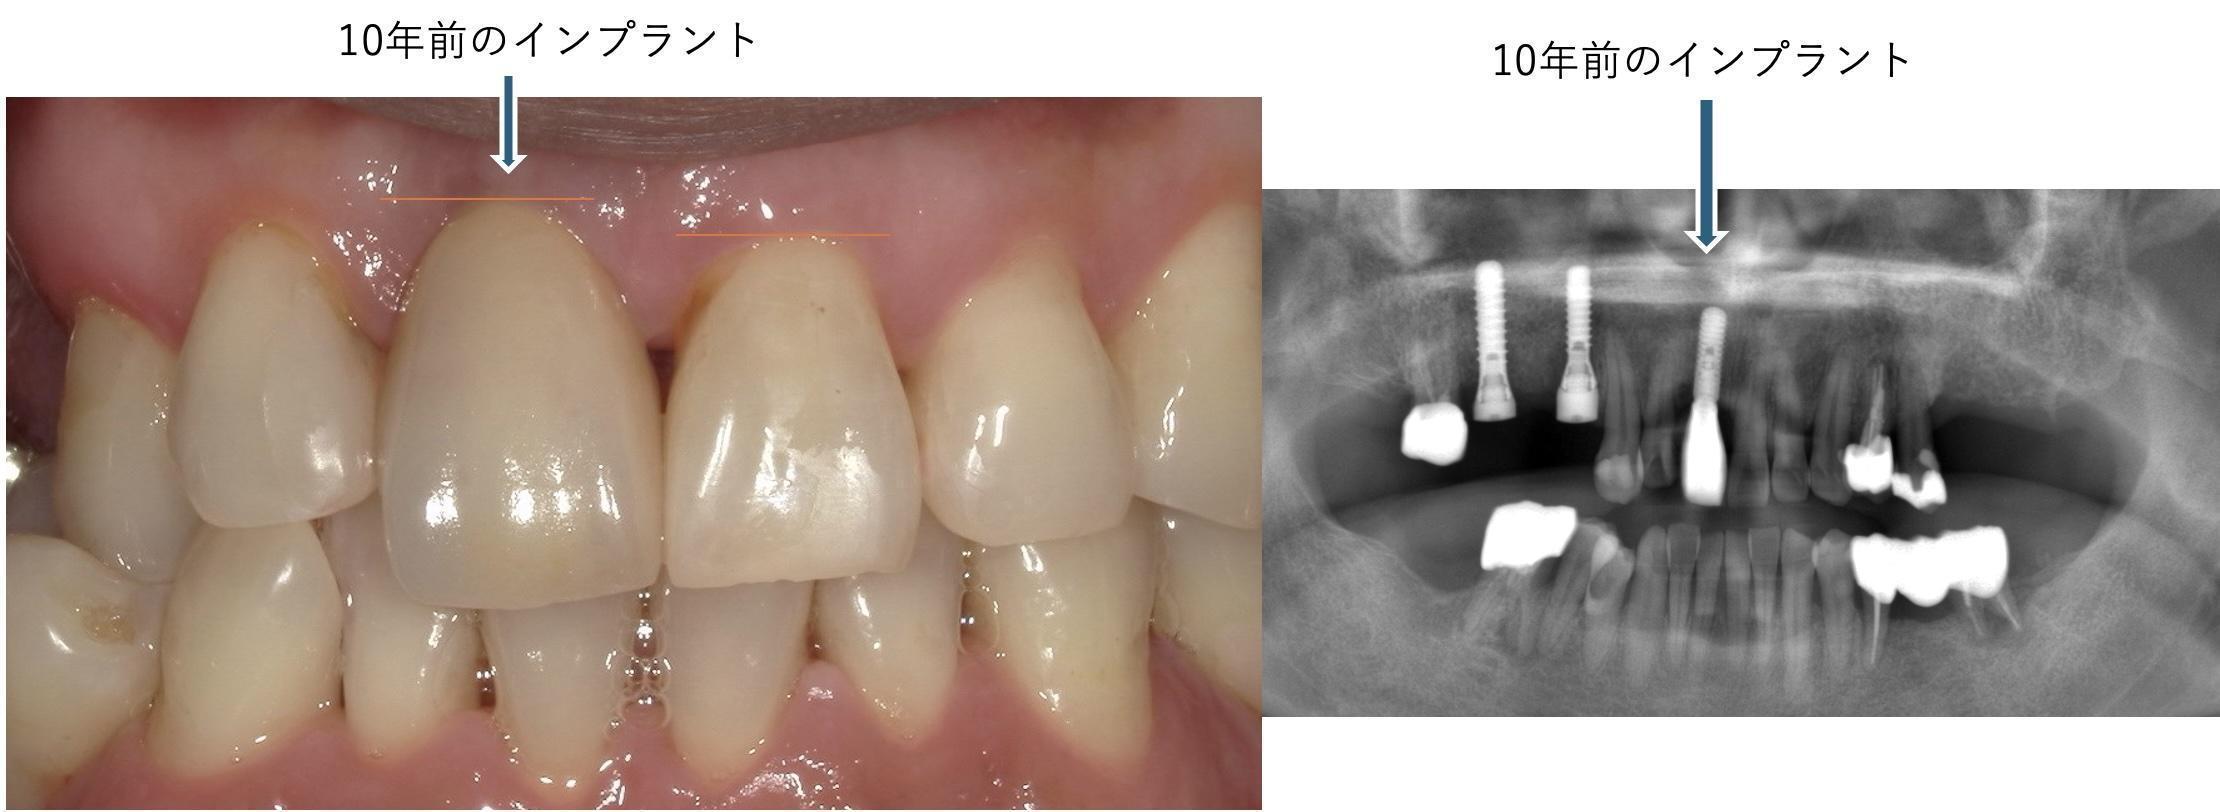

こちらの患者様は他院でインプラント治療を受けたあと、メインテナンスを当院で担当しております。

最初は全顎的に歯茎が赤く、触ったら出血するような状態でしたが、歯科衛生士が一生懸命二人三脚で

口腔衛生管理に勤め、現在では歯肉の炎症が落ち着いてきており、口腔内衛生状態は改善されました。

インプラントについては、もともと歯肉ラインは天然歯よりも下にありましたが、そこから変わっておらず、

10年もっております。先日、インプラントが動いていることに気がついて、土台と歯の接着が緩んでいることに気がついたので

歯をはずして、キレイに洗浄して、再接着修理して、元通りキレイな状態に戻っています。